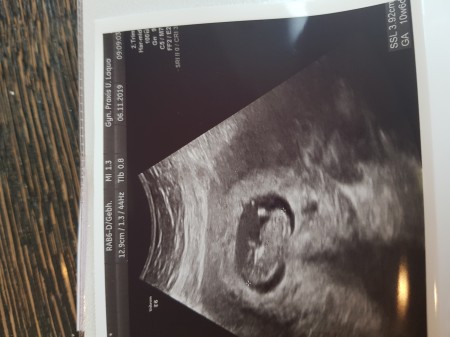

Tahminlerinizi alabilirmiyim fotoda 11haftalik simdi 12+3üm cok heyecanliyiz persembe günü doktor randevum var ama ozamana kadar sizinde tahmininizi alabilirmiyim

Gebelik haftası 12+3

Cinsiyetini merak ediyoruz süpriz bir bebek oldu spiralle hamile kaldim 2kizim 1oglum var ama yinede cinsiyetini merak ediyoruz önemli olan saglikli olmasi ama yinede merak icindeyiz

Canım aynı benim bebişin görüntüsü :)

Aminn canım inşallah eğer öğrenirsen burayada yaz inşallah belki benzerlikten cinsiyet aynı çıkar :))ben benzettim,ama sizce

Benziyor evet persembe randevum 11haftalik gittigimde 2hafta sonra gel söyliyim dedi ögrenince yazarim